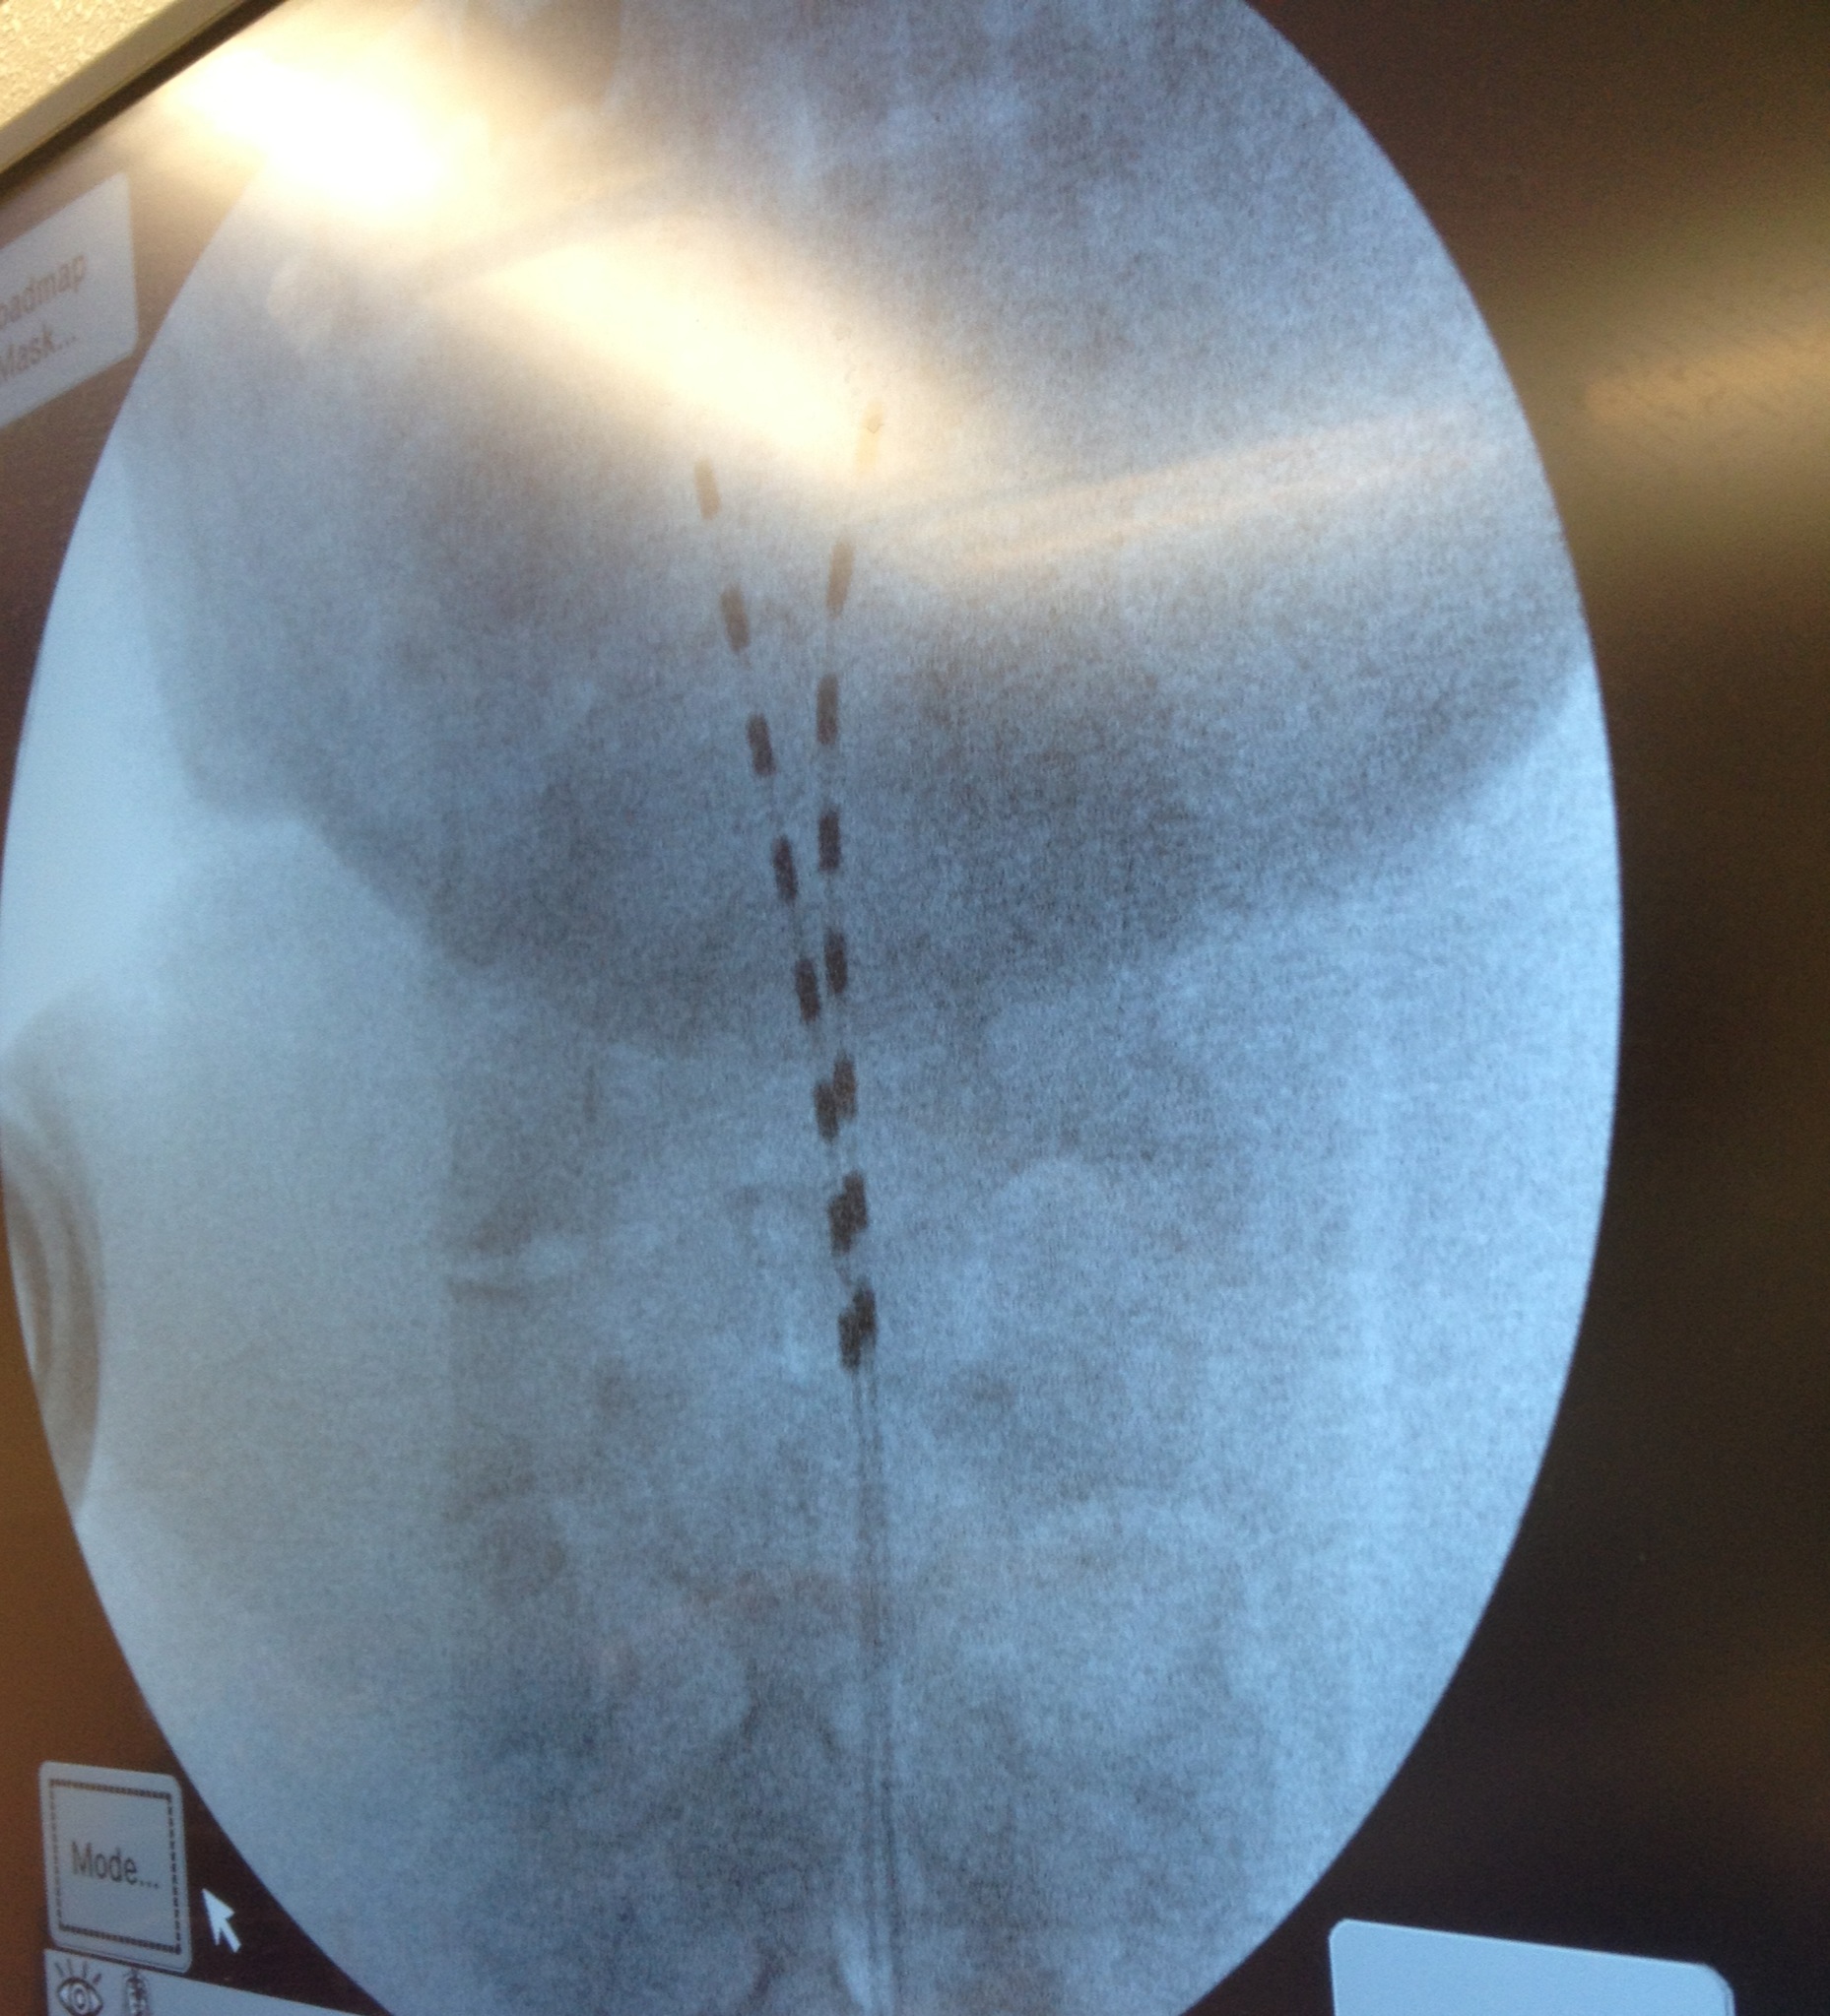

I was awake for nearly all of the approximately 200 minute procedure, but I was not able to see just how involved the surgery was. For those considering neurostimulators, do not let the photo below scare you. They gave me really good meds. There was little to no pain involved and you need to be awake to help them best direct the placement of the electrodes. As those who know me might expect, I even thought I had some of my best stand up lines going while they were doing this. The key word is “thought.”

I am a long ways from a final determination of how much elevation I will get from having two neurostimulators implanted under the skin on my backside and 32 electrodes running up and down my spine, but here’s my initial read on how the surgery went.

The two implants are already producing encouraging results. The severe pain I have lived with for some time in my right arm and left leg has certainly declined. My toes–which more often than not have felt like a UFC fighter stomped on them before smashing them with a super sized sledgehammer–have been completely free of pain ever since the surgery. The toe pain was a result of nerve damage I suffered when I broke a vertebrae and wore away a disc or two in my lower back. Two major lumber surgeries did not result in any major pain level reduction or increase in the function of my left leg. It did, however, leave me with titanium screws and rods.